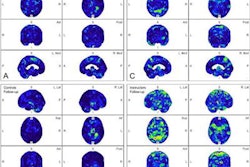

In athletes with sports-related concussions, increased neuroinflammation was observed on PET in medial temporal lobes, and tau aggregation was observed in the corpus callosum. In TBI patients, widespread white matter tau aggregation and neuroinflammation were found.